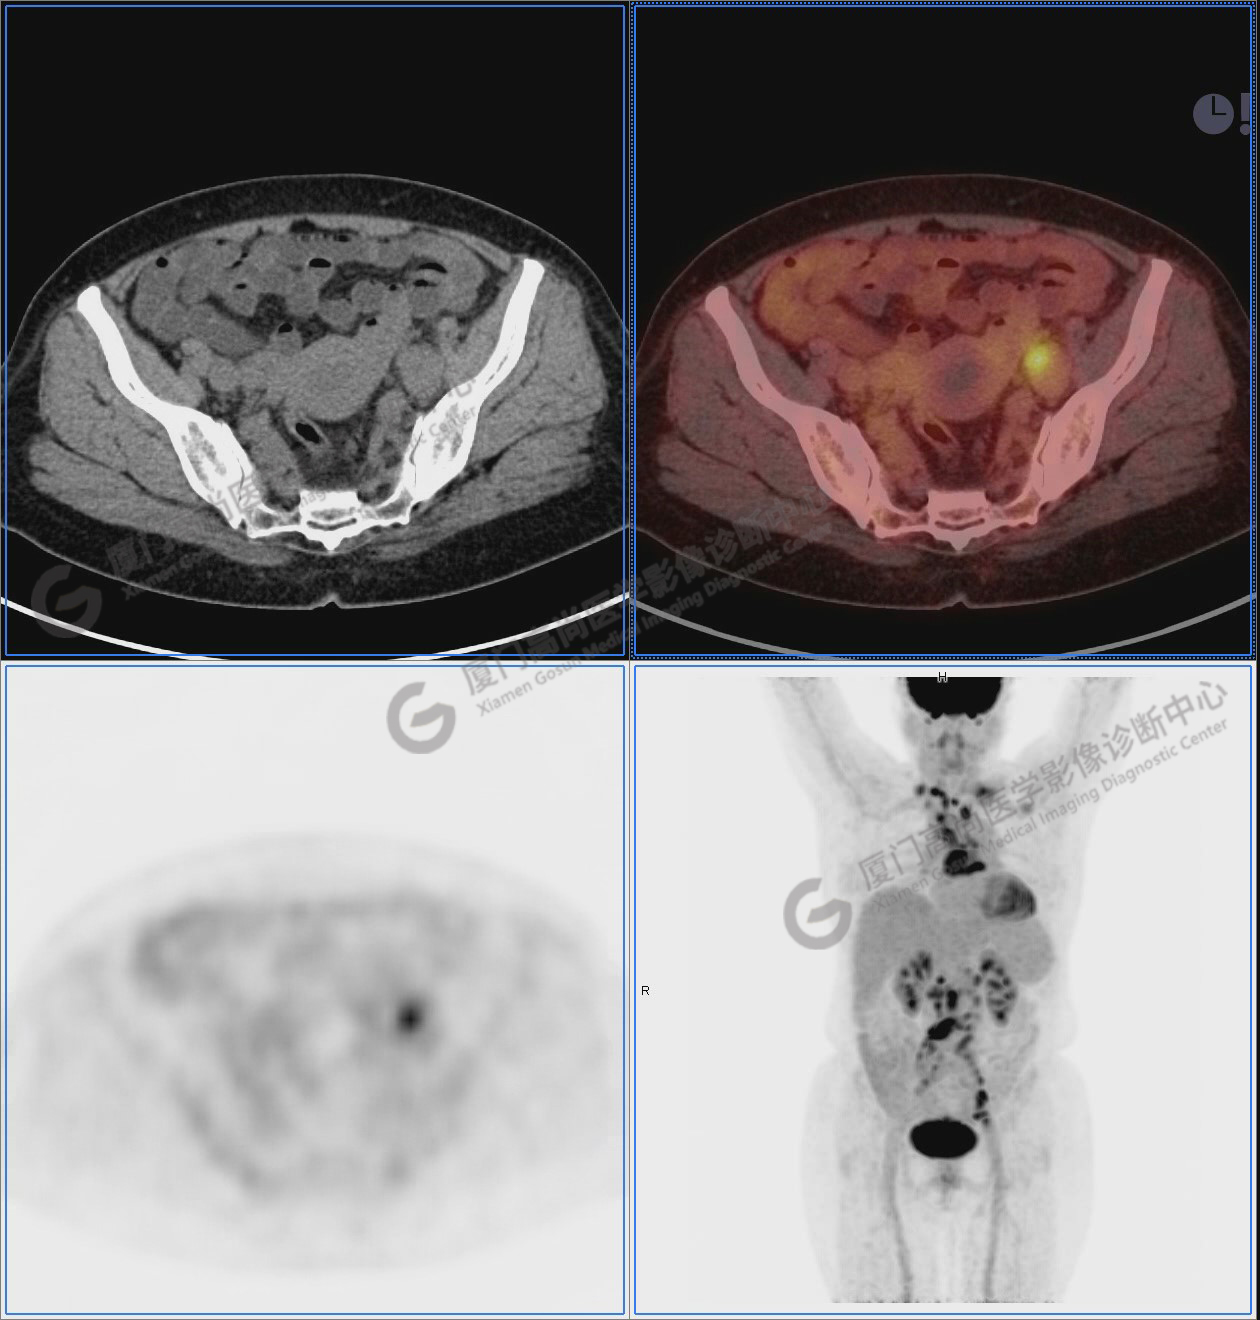

圖10-11:子宮頸軟組織腫塊,代謝異常增高,考慮為宮頸癌。

圖10

圖11

圖12-13:延遲2小時后,宮頸腫塊糖代謝進一步增高。

圖12

圖13